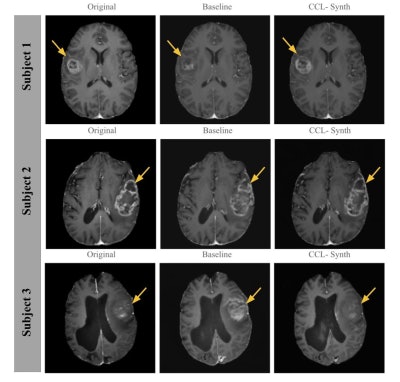

Comparison of T1-CE images generated by the CCL-Synth model with ground truth and baseline results for three subjects. Yellow arrows indicate key regions where the CCL-Synth model achieves improved tumor conspicuity, enhancing visualization of tumor margins and internal structures compared to the baseline. Images and caption courtesy of Lavanya Umapathy, PhD, and the ISMRM.

The study's overall finding was that integrating tissue-specific MR contrast information in the synthesis of contrast-enhanced images improved image-quality evaluation metrics such as the structural similarity index measure (SSIM), the peak signal-to-noise ratio (PSNR), and learned perceptual image patch similarity (LPIPS), Umapathy said, noting that the approach "leverages multicontrast MR images to capture tissue-specific information through a self-supervised contrastive learning framework."

"Despite the technical challenges in synthesizing accurate and high-quality images, our deep learning approach demonstrated the feasibility of generating reliable T1-weighted contrast-enhanced images without the need for gadolinium injection," she concluded. "By leveraging prior information about underlying tissues through a self-supervised pre-training approach, our synthesis model achieves high perceptual quality and fidelity in synthesized images."